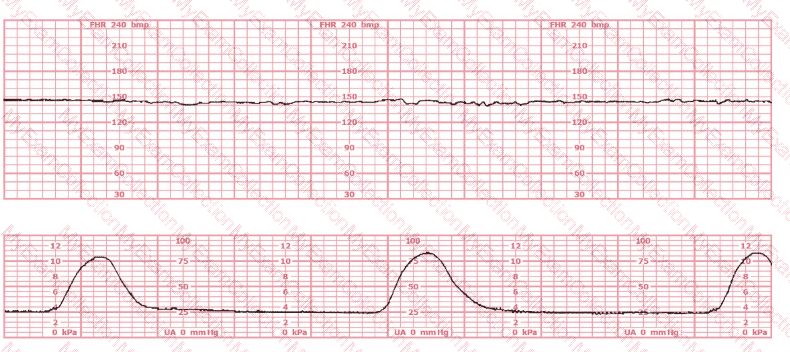

A woman is being induced with oxytocin. The tracing shown is representative of 20 minutes. Based on this tracing, the next step would be to: